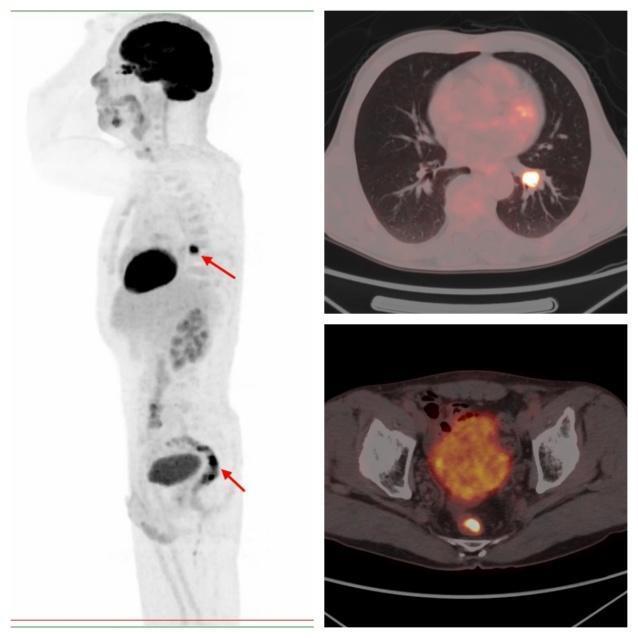

图片

病例2,PET/CT示左肺下叶、直肠代谢异常,符合双原发癌;之后患者行支气管镜下活检,病理证实原发肺鳞癌;行肠镜下活检,病理证实为原发直肠溃疡型腺癌。